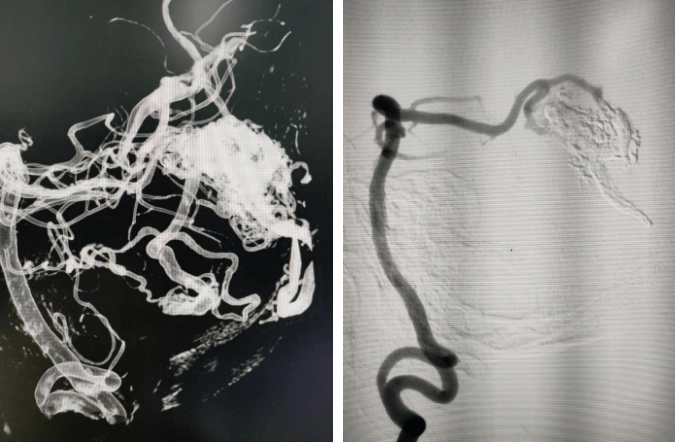

開顱夾閉動脈瘤手術(shù)

支架輔助動脈瘤栓塞術(shù)前、術(shù)后對比

術(shù)前血管畸形及介入治療后血管畸形消失(治愈出院)